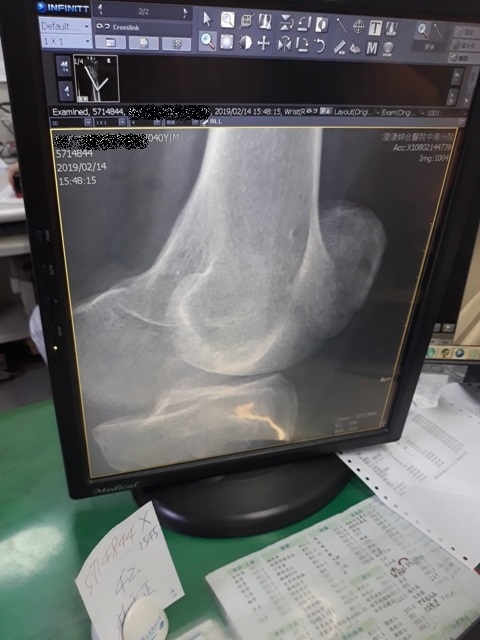

右手X光↓

進入門診前,我自認為手比腳恢復還快,因為比起一開始,手指比較能出力了,手腕可轉動的範圍也變大了。腳因一直用副木石膏固定住,不能動,所以也不知恢復多少。進入門診後,黃醫師說斷裂的骨頭都沒移位。手沒什麼進展(骨頭不會長那麼快),腳的部份下回再來復診時,可能會恢復的較快了。

手沒什麼進展這件事,讓我比較吃驚,詢問黃醫師,手如果也改用副木,會不會比較好,黃醫師說,他個人是認為沒什麼差。他看著X光片照出來的結果,說開刀或不開刀他覺得都差不多。